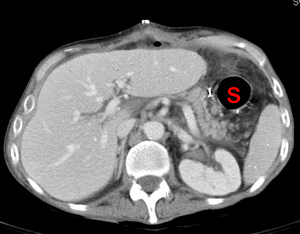

The gastric remnant (S) after a partial gastrectomy. This situation does not usually permit transillumination for endoscopic gastrostomy tube placement and requires CT guidance due to the distance from the abdominal wall and the smaller target.